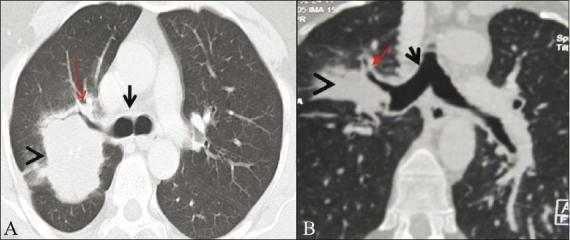

Fifty-six patients were selected for analysis based on the detection of major airway lesions on fiber-optic bronchoscopy (FB) or routine axial images. Comparisons were made between axial images, virtual bronchoscopy (VB), minimal-intensity projection (minIP), and multiplanar reformatted (MPR) images using FB as the gold standard. Lesions were evaluated in terms of degree of airway narrowing, distance from carina, length of the narrowed segment and visualization of airway distal to the lesion.

MPR images had the highest degree of agreement with FB (Κ = 0.76) in the depiction of degree of narrowing. minIP had the least degree of agreement with FB (Κ = 0.51) in this regard. The distal visualization was best on MPR images (84.2%), followed by axial images (80.7%), whereas FB could visualize the lesions only in 45.4% of the cases. VB had the best agreement with FB in assessing the segment length (Κ = 0.62). Overall there were no statistically significant differences in the measurement of the distance from the carina in the axial, minIP, and MPR images. MPR images had the highest overall degree of confidence, namely, 70.17% (n = 40).

Three-dimensional reconstruction techniques were found to improve lesion evaluation compared with axial images alone. The technique of MPR images was the most useful for lesion evaluation and provided additional information useful for surgical and airway interventions in tracheobronchial stenosis. minIP was useful in the overall depiction of airway anatomy.

基于纤维支气管镜检查(FB)或常规轴向图像上检测到的大气道病变,选取56例患者进行分析。以FB作为金标准,对轴向图像、虚拟支气管镜检查(VB)、最小密度投影(minIP)和多平面重组(MPR)图像进行比较。从气道狭窄程度、距隆突的距离、狭窄段长度以及病变远端气道的可视化情况等方面对病变进行评估。

在描绘狭窄程度方面,MPR图像与FB的一致性程度最高(Κ = 0.76)。在这方面,minIP与FB的一致性程度最低(Κ = 0.51)。MPR图像上病变远端的可视化效果最佳(84.2%),其次是轴向图像(80.7%),而FB仅能在45.4%的病例中看到病变。在评估节段长度方面,VB与FB的一致性最佳(Κ = 0.62)。总体而言,轴向图像、minIP图像和MPR图像在测量距隆突的距离方面无统计学显著差异。MPR图像的总体置信度最高,为70.17%(n = 40)。

与单纯的轴向图像相比,发现三维重建技术可改善病变评估。MPR图像技术在病变评估中最有用,并为气管支气管狭窄的手术和气道干预提供了额外的有用信息。minIP在气道解剖结构的整体描绘中很有用。